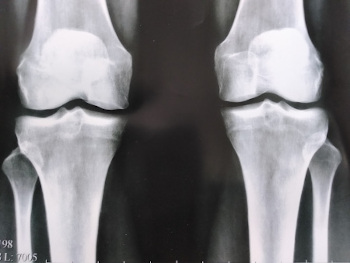

Utjecaj artroze na hrskavično tkivo koljenskog zgloba.